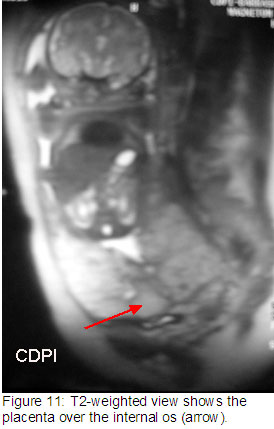

Клиника де Diagnóstico пор Imagem (CDPI), Институт Fernandes Figueira (IFF) - FIOCRUZ